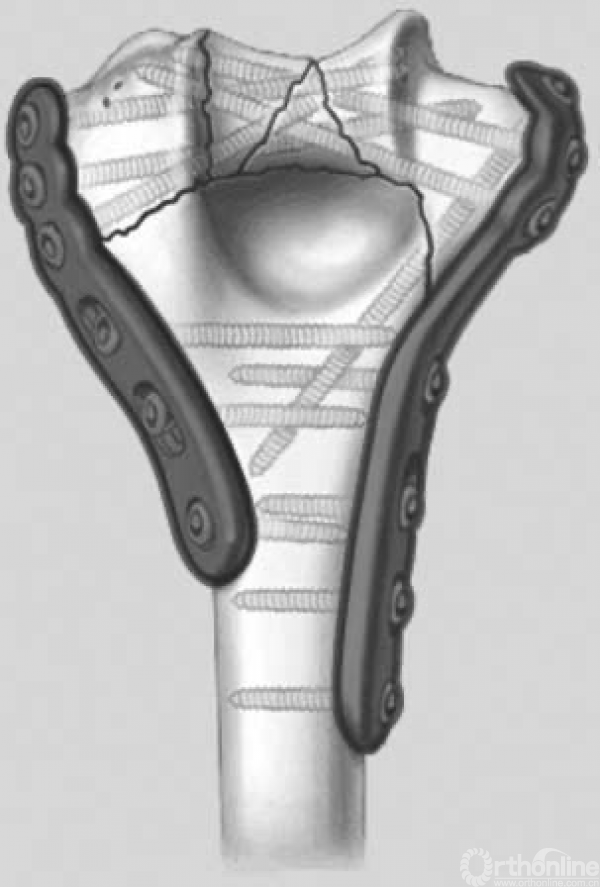

图9 拱形结构刚性连接双柱的稳定性。这种拱形结构在插入基石之前是不稳定的,螺钉彼此交锁相当于在两个柱末端形成了拱形结构,内外侧柱上各自的坚固钢板通过这种拱形结构联结在一起,交叉螺钉相当于拱门的基石。这是由于这种结构的稳定性,粉碎性肱骨远端骨折或合并骨质疏松的患者能获得良好的内在稳定性。在插入“基石”,即放置彼此交锁的螺钉之前,这种结构是不稳定的。